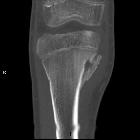

CT

- central intramedullary hypodense cystic lesion with thick rim ossification

- extensive thick well-circumscribed periosteal reaction and bone sclerosis around the lesion could be seen